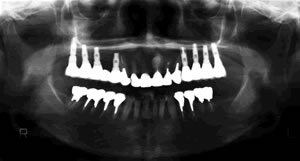

当院では1987年にITIストローマンインプラントによる部分欠損への応用、 また1989年にブローネマルクインプラント用いた無歯顎インプラント治療 (歯がすべてなくなった人へのインプラント治療)を開始しました。

現在までに約2000本のインプラント治療を34年ほど前から行っております。当時はインプラント治療といってもまだ一般的ではなく、「そんな治療聞いたことがない」とおっしゃる患者様が多く、インプラント治療をお受けになる方は少なかったです。最近では「私の場合はどんな治療がいいのですか?入れ歯かインプラントかどっちがいいですか?」と、ご相談にいらっしゃる患者様が増えています。

私は歯科医師として患者様にいろいろな治療の選択肢をご提供できるように常に努力をしていきたいと考えており、 インプラント治療はその選択肢の一つだと思います。当院ではより正確に、安全にインプラント手術が行えるようにCTスキャンを応用した診断法を1996年から始めました。 CTスキャンは通常は大きな医科の病院にしか設置されていません。 以前はそういった病院に患者様に行ってもらい撮影をしておりました。 しかし現在では歯科用のCTスキャンが開発され、当院にも2008年4月にプレヴィスタと言うコーンビームCTが設置されました。これによりインプラントのCT撮影、手術シュミレーション検査がいつでもできるようになりました。 難症例を除き、撮影後少しお待ちいただければインプラント治療が可能かどうかご説明できます。患者様もこのCT画像をご覧になると、インプラント治療がどのようなものか良くわかると思います。インプラント治療に関心のある方はお気軽にご相談ください。